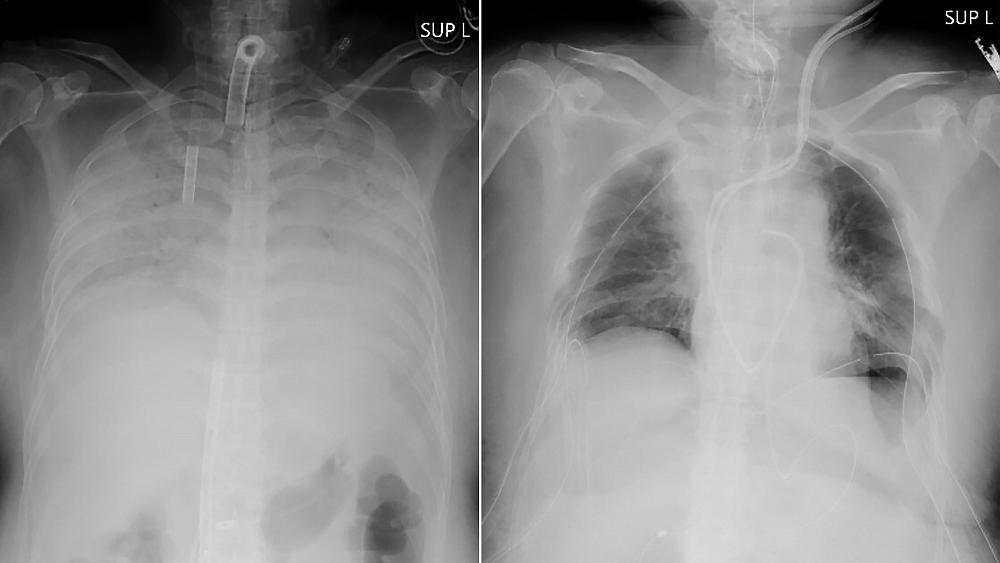

The woman contracted COVID-19 late last year and developed breathing difficulties that rapidly worsened. She was placed on a life support machine that works as an artificial lung for more than three months at another hospital because her lungs were so severely damaged.

Even after she was free of the virus, her lungs were no longer functional or treatable, and the only option for her to live was to receive a lung transplant, the university said.